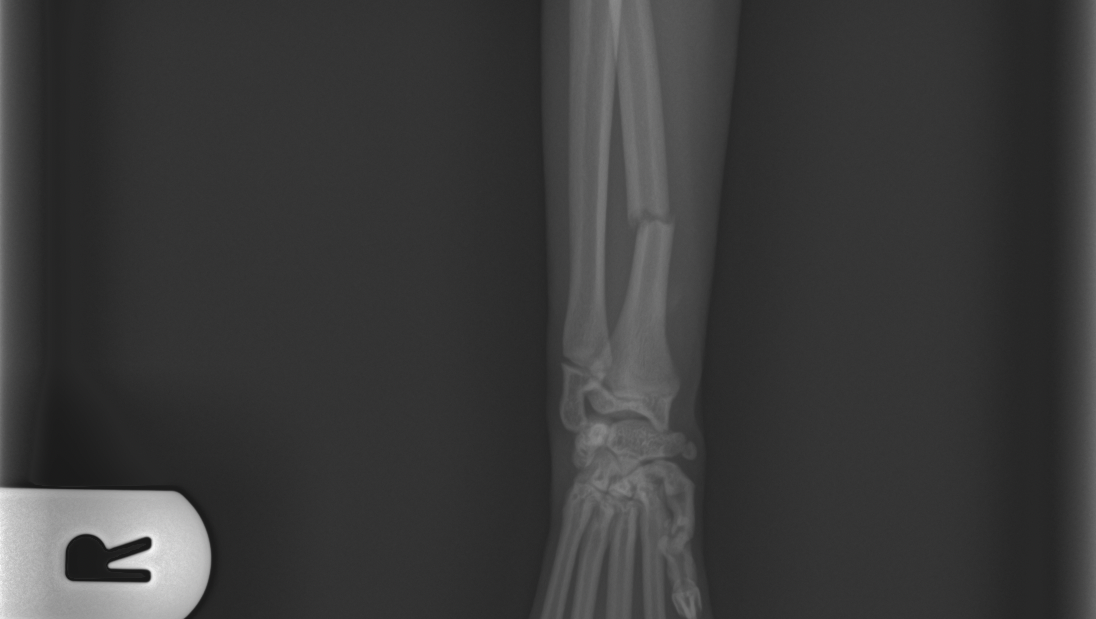

Levamo-lo de imediato ao veterinário, onde foi feita uma ecografia abdominal que, felizmente, não mostrou alterações internas. No entanto, o raio-x revelou fraturas, no rádio da pata dianteira direita e no metacarpo da pata dianteira esquerda.